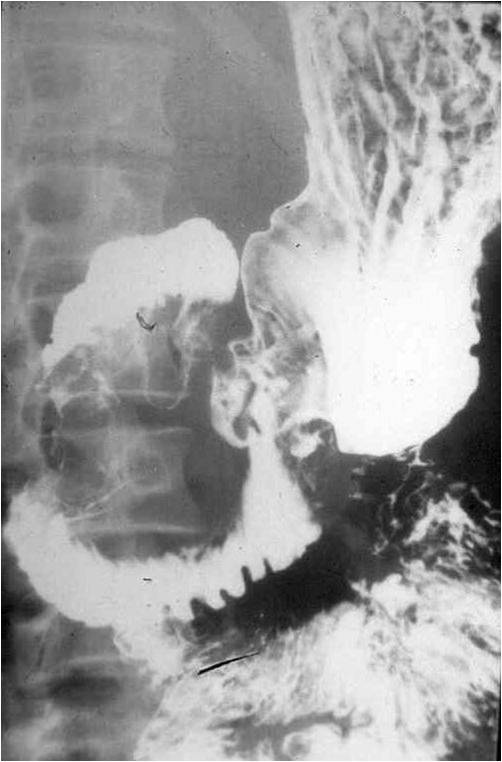

Image

Fig.22. Crohn’s disease

Radiographic findings: Most frequently luminal narrowing of the terminal ileum is detected. The wall is thickened, intramural and inter-intestinal fistulas may develop. The abdominal plain film is not suitable for identification of abdominal abscesses.